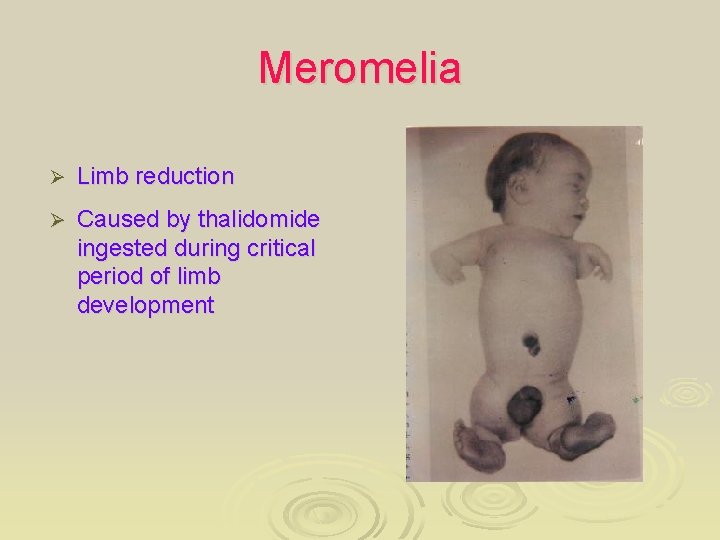

Amelia and meromelia Ø A) Quadruple amelia (comlete absence of the upper and lower limbs). Ø B, C) meromelia (partial absence) of the upper limb. Ø caused by thalidomide.

Various types of meromelia Ø Partial absence of limbs (disturbance of growth of limb) Ø A) absence of hands and most of fore-arms Ø B) absence of the digits Ø C) absence of the hand Ø D) absence of the fourth and fifth digits, syndactyly of the second and third digit Ø E) absence of third digit, cleft hand Ø F) absence of second and third toes, syndactyly of fourth and fifth toes

Meromelia Ø Limb reduction Ø Caused by thalidomide ingested during critical period of limb development